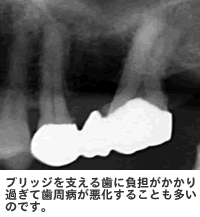

両側の歯を削って支えにしてブリッジをかけた状態しかし、ブリッジにも問題点がいくつかあります。まず、支える歯の周囲を削って被せ物をするので、健康な歯を削らなければならないというデメリットがあります。

ブリッジとは結局、どんなに小さなブリッジでも、1本無くなってしまった歯を両隣の歯で支え、これまでは3本でこなしていた仕事を2本でこなすことになります。少しの間であれば、頑張ることもできそうですが、支えている歯には大きな負担がかかり、状態にもよりますが10年ぐらい経つと支えている歯が耐え切れなくなる場合もあるようです。

ブリッジを支える歯に負担がかかる2つ目は、取り外し式の入れ歯です。保険内の義歯は非常に安く、手軽に作ることができます。しかし、入れ歯には様々なデメリットがあります。